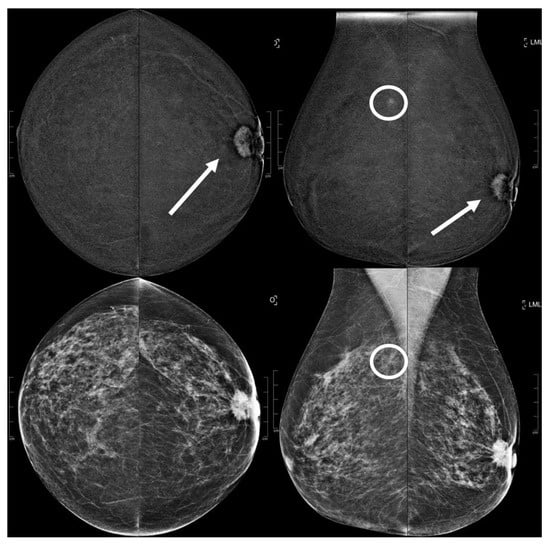

Figure 5.

A 51 year old patient. Contrast-enhanced digital mammography performed as preoperative staging for a B5 lesion in the right breast (arrows). In the early RC in the left breast, there was an enhancing asymmetry in the inner quadrants with moderate conspicuity only visible in CC (circle), corresponding to an opacity in low-energy images. This opacity subsequently underwent VABB (tomosynthesis-guided vacuum assisted breast biopsy), which confirmed an invasive carcinoma.